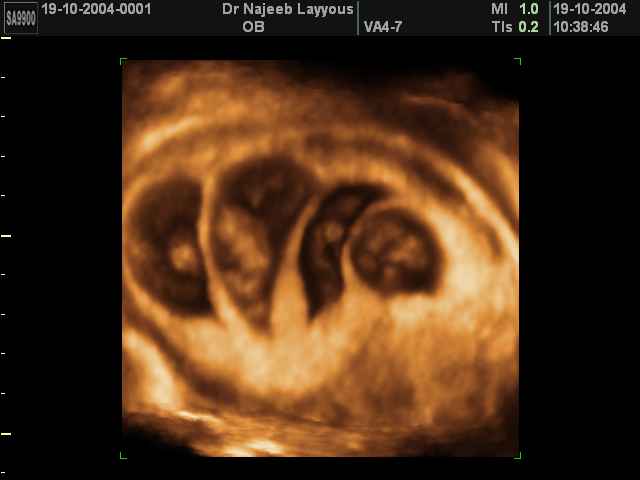

صور لتوائم بجهاز الالتراساوند ثلاثي الأبعاد | الدكتور نجيب ليوس

صور لتوائم بجهاز الموجات فوق صوتية ثلاثي الأبعاد